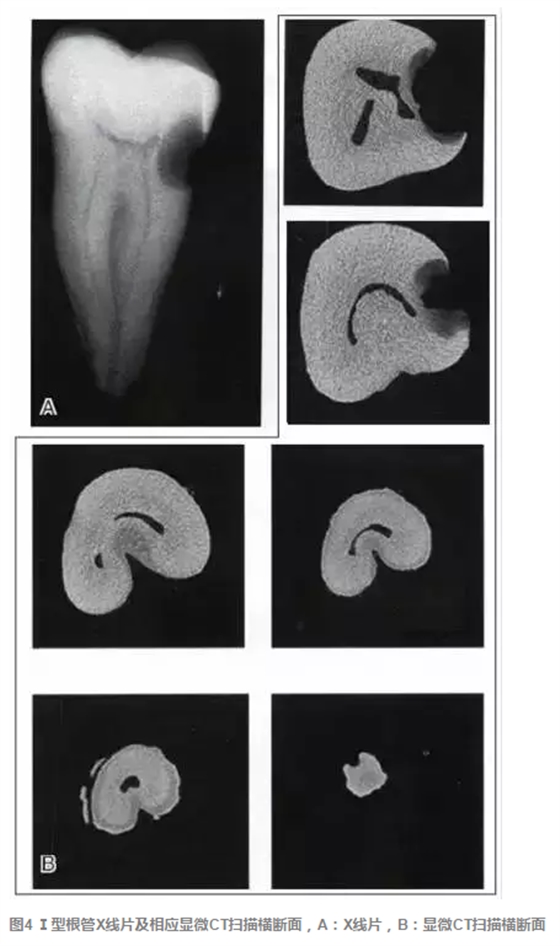

傳統(tǒng)的Melton C形根管分類法雖深化了對(duì)根管結(jié)構(gòu)的認(rèn)識(shí),但由于是基于組織學(xué)的分類,不能指導(dǎo)臨床實(shí)踐。有學(xué)者基于C形根管X 線特征,結(jié)合顯微CT掃描結(jié)果,提出了一種新的分類方法,便于臨床應(yīng)用。這種分類方法將下頜第二磨牙分為3型:①Ⅰ型:融合型,X線片上見(jiàn)2個(gè)根管,但在根尖區(qū)融合;②Ⅱ型:分離型,X線片上見(jiàn)2個(gè)根管且相互獨(dú)立;③ Ⅲ型:不對(duì)稱型,X線片上雖有2個(gè)根管相互獨(dú)立,但一長(zhǎng)一短,互不對(duì)稱(圖3)。各類型C形根管X線特征、顯微CT掃描及重建結(jié)果見(jiàn)圖4~9。